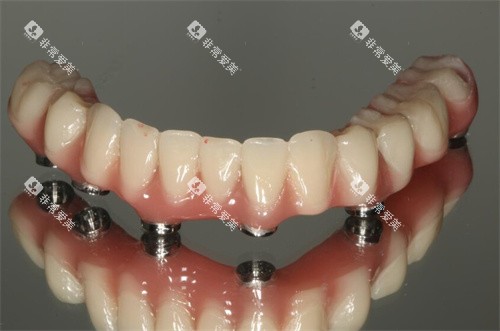

All-on-4/6:用4-6颗种植体支撑全口牙,比传统种植省2-4万,但需严格评估牙槽骨条件。